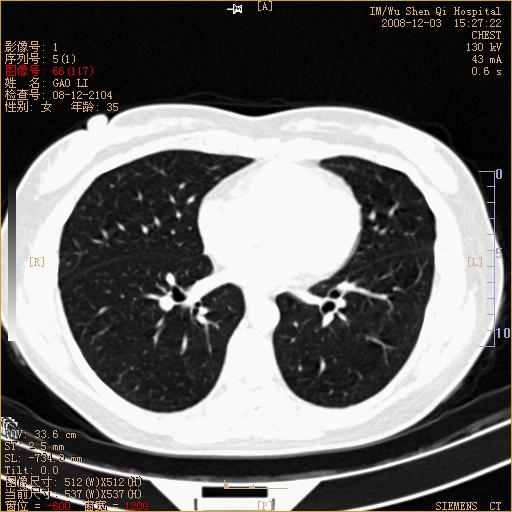

标题: CT16895:女,35岁,反复咳嗽数月,只传部分图像,是否考虑 [打印本页]

标题: CT16895:女,35岁,反复咳嗽数月,只传部分图像,是否考虑

左下肺支扩

典型“印戒征”。

印戒征,支持支扩.

左下肺扩支

印戒征,支扩